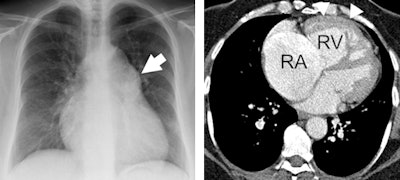

ECR 2016 delegates will also be reminded of the subtle information available on CT and MR such as abnormal shape (D-shaping) of the interventricular septum, which may indicate pulmonary pressure overload or how thickened interlobular septae and pulmonary ground-glass opacities on CT may point to pulmonary congestion secondary to heart failure.

In many patients with pulmonary diseases, the final lethal event is right heart failure. This occurs because the right ventricle, which supplies blood to the pulmonary artery, is not designed to cope with pressure overload associated with pulmonary hypertension.

Today the most relevant parameter for right ventricular function is measuring the ejection fraction by means of MRI. This parameter, which indicates how much percentage of its volume the heart can eject with each beat, is easy to measure and is an excellent parameter to predict outcome and to guide and monitor therapy, according to Dr. Jens Bremerich, head of the division of cardiothoracic imaging at the University Hospital of Basel in Switzerland. He will be presenting perspectives from cardiac imaging, specifically the role of the heart in cardiopulmonary disease.